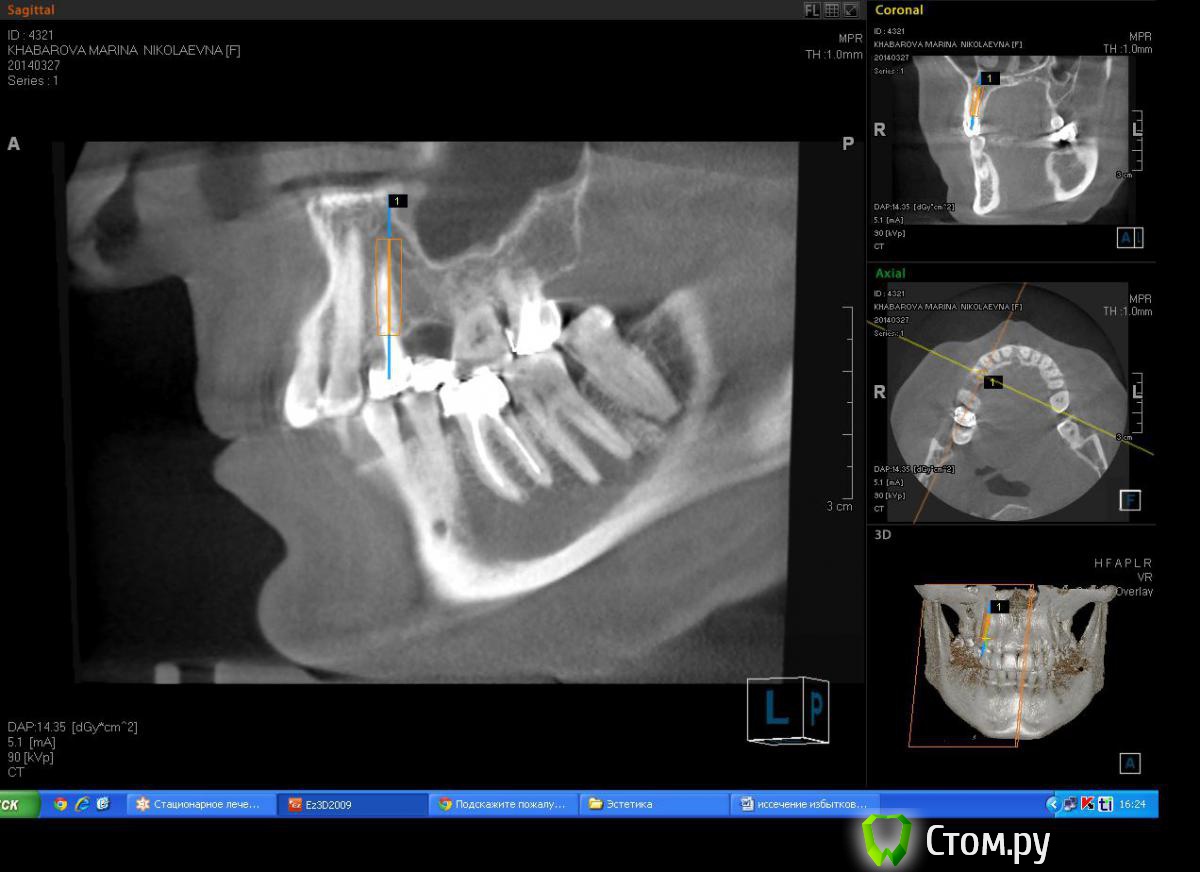

Milanomoda Опубликовано 22 апреля, 2014 Поделиться Опубликовано 22 апреля, 2014 Здравствуйте, уважаемые коллеги. Вообщем обратилась за помощью пациентка - в области 14 зуб, от него консоль на 15, посоветовавшись с ортопедом, приняли решение удалить 14 зуб и одномоментно в лунку имплант, в это же посещение имплантация в области 15. Подскажите пожалуйста с тактикой, можно ли в данном случае рассматривать одномоментную методику имплантации ? Заранаее с пасибо ) Снимки КТ прикладываю. Ссылка на комментарий

Milanomoda Опубликовано 22 апреля, 2014 Автор Поделиться Опубликовано 22 апреля, 2014 Имплантацию в районе 14 зуба планирую ставить в область язычного корня, только вот вопросик такой, при одномоментном протоколе на сколько примерно заглублять нужно будет имплант? Ссылка на комментарий

Milanomoda Опубликовано 22 апреля, 2014 Автор Поделиться Опубликовано 22 апреля, 2014 Картина с планируемым 4.2 х 16 мм имплантом в области 14. Ссылка на комментарий